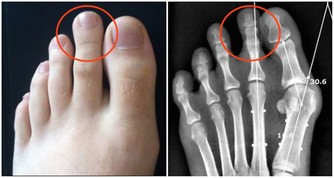

如果留意到自己的嘴角總是出現口瘡,而且全身產生了疼痛感,有可能是缺乏維生素B2引起。維生素B2是人體需要的重要營養物質,又稱為核黃素,如果出現了維生素B2明顯缺乏這種現象,很容易有上火表現,此時嘴角就容易出現口瘡,而且會伴隨著口腔潰瘍這種現像出現。

為了改善這些不良表現,最重要的就是及時補充營養物質,從飲食過程中獲取人體需要的B族維生素,這樣身體維持健康狀態,才能防止不良症狀出現。